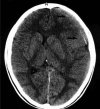

Figure 1.

Figure 1.. Computed Tomography (CT) scan showing the presence of subdural haematoma in the right frontotemporal region (arrows)